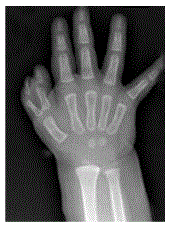

A duplicação acima do polegar é considerada uma polidactilia ___________ e classificada como tipo ___ segundo Wassel.